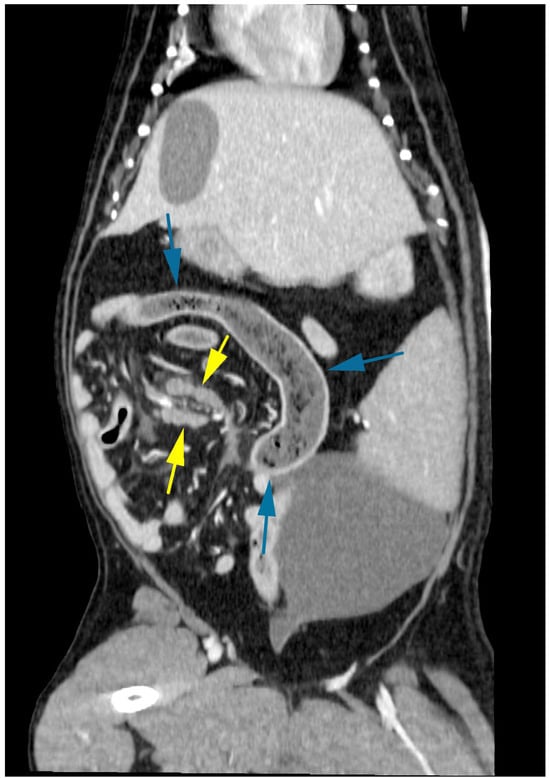

On presentation, the dog was mildly depressed, weighed 20.3 kg, and had a body condition of 6/9. Her rectal temperature was 37.7 degrees, her heart rate was 100 beats per minute, and her respiratory rate was 32 breaths per minute. Her mucous membranes were pink, mildly injected, and moist with normal capillary refill (<1 s). The abdomen was tense, and there was marked pain and vocalisation with mid-abdominal palpation. Packed cell volume and total solids were within normal limits at 43% (37–55%) and 75 g/L (reference range, 55–75 g/L), respectively. A complete blood count (IDEXX ProCyte Dx, Westbrook, ME, USA) and biochemistry (IDEXX Catalyst One, Westbrook, ME, USA) were within normal limits. Venous blood gas analysis (Radiometer, Copenhagen, Denmark) revealed mild hypercapnia (pCO2 44.7, range 34.0–39.0), mild hypokalaemia (3.3, range 3.4–5.3), and mild hyperglycaemia (6.7, range 3.6–6.2). Lactate was within normal limits. Ultrasound-guided abdominocentesis was performed, and the abdominal fluid collected was an acellular high-protein transudate with a total protein of 43 g/L (refractometer). The dog was hospitalised for initial supportive care. An intravenous (IV) catheter was placed, and a lactated ringer solution supplemented with 10 mmol potassium chloride was administered at a rate of 100 mL/h. A fentanyl constant rate infusion was started at 3 ug/kg/h, and maropitant 1 mg/kg was administered IV. Three-view abdominal radiographs were performed to identify a moderate amount of gas and fluid within the stomach and intestines with mild dilation of both organs (Figure 1). No foreign body was identified, and faeces were present within the colon. There were good serosal details, and the findings were not conclusive of an obstructive pattern. Differential diagnoses included radiolucent gastric or intestinal foreign bodies, gastroenteritis, acute pancreatitis, or peritonitis.

Figure 1. Abdominal radiographs revealed dilated intestines and mixed heterogeneous gas and soft tissue attenuating material within the stomach without evidence of a foreign body or obstructive pattern.